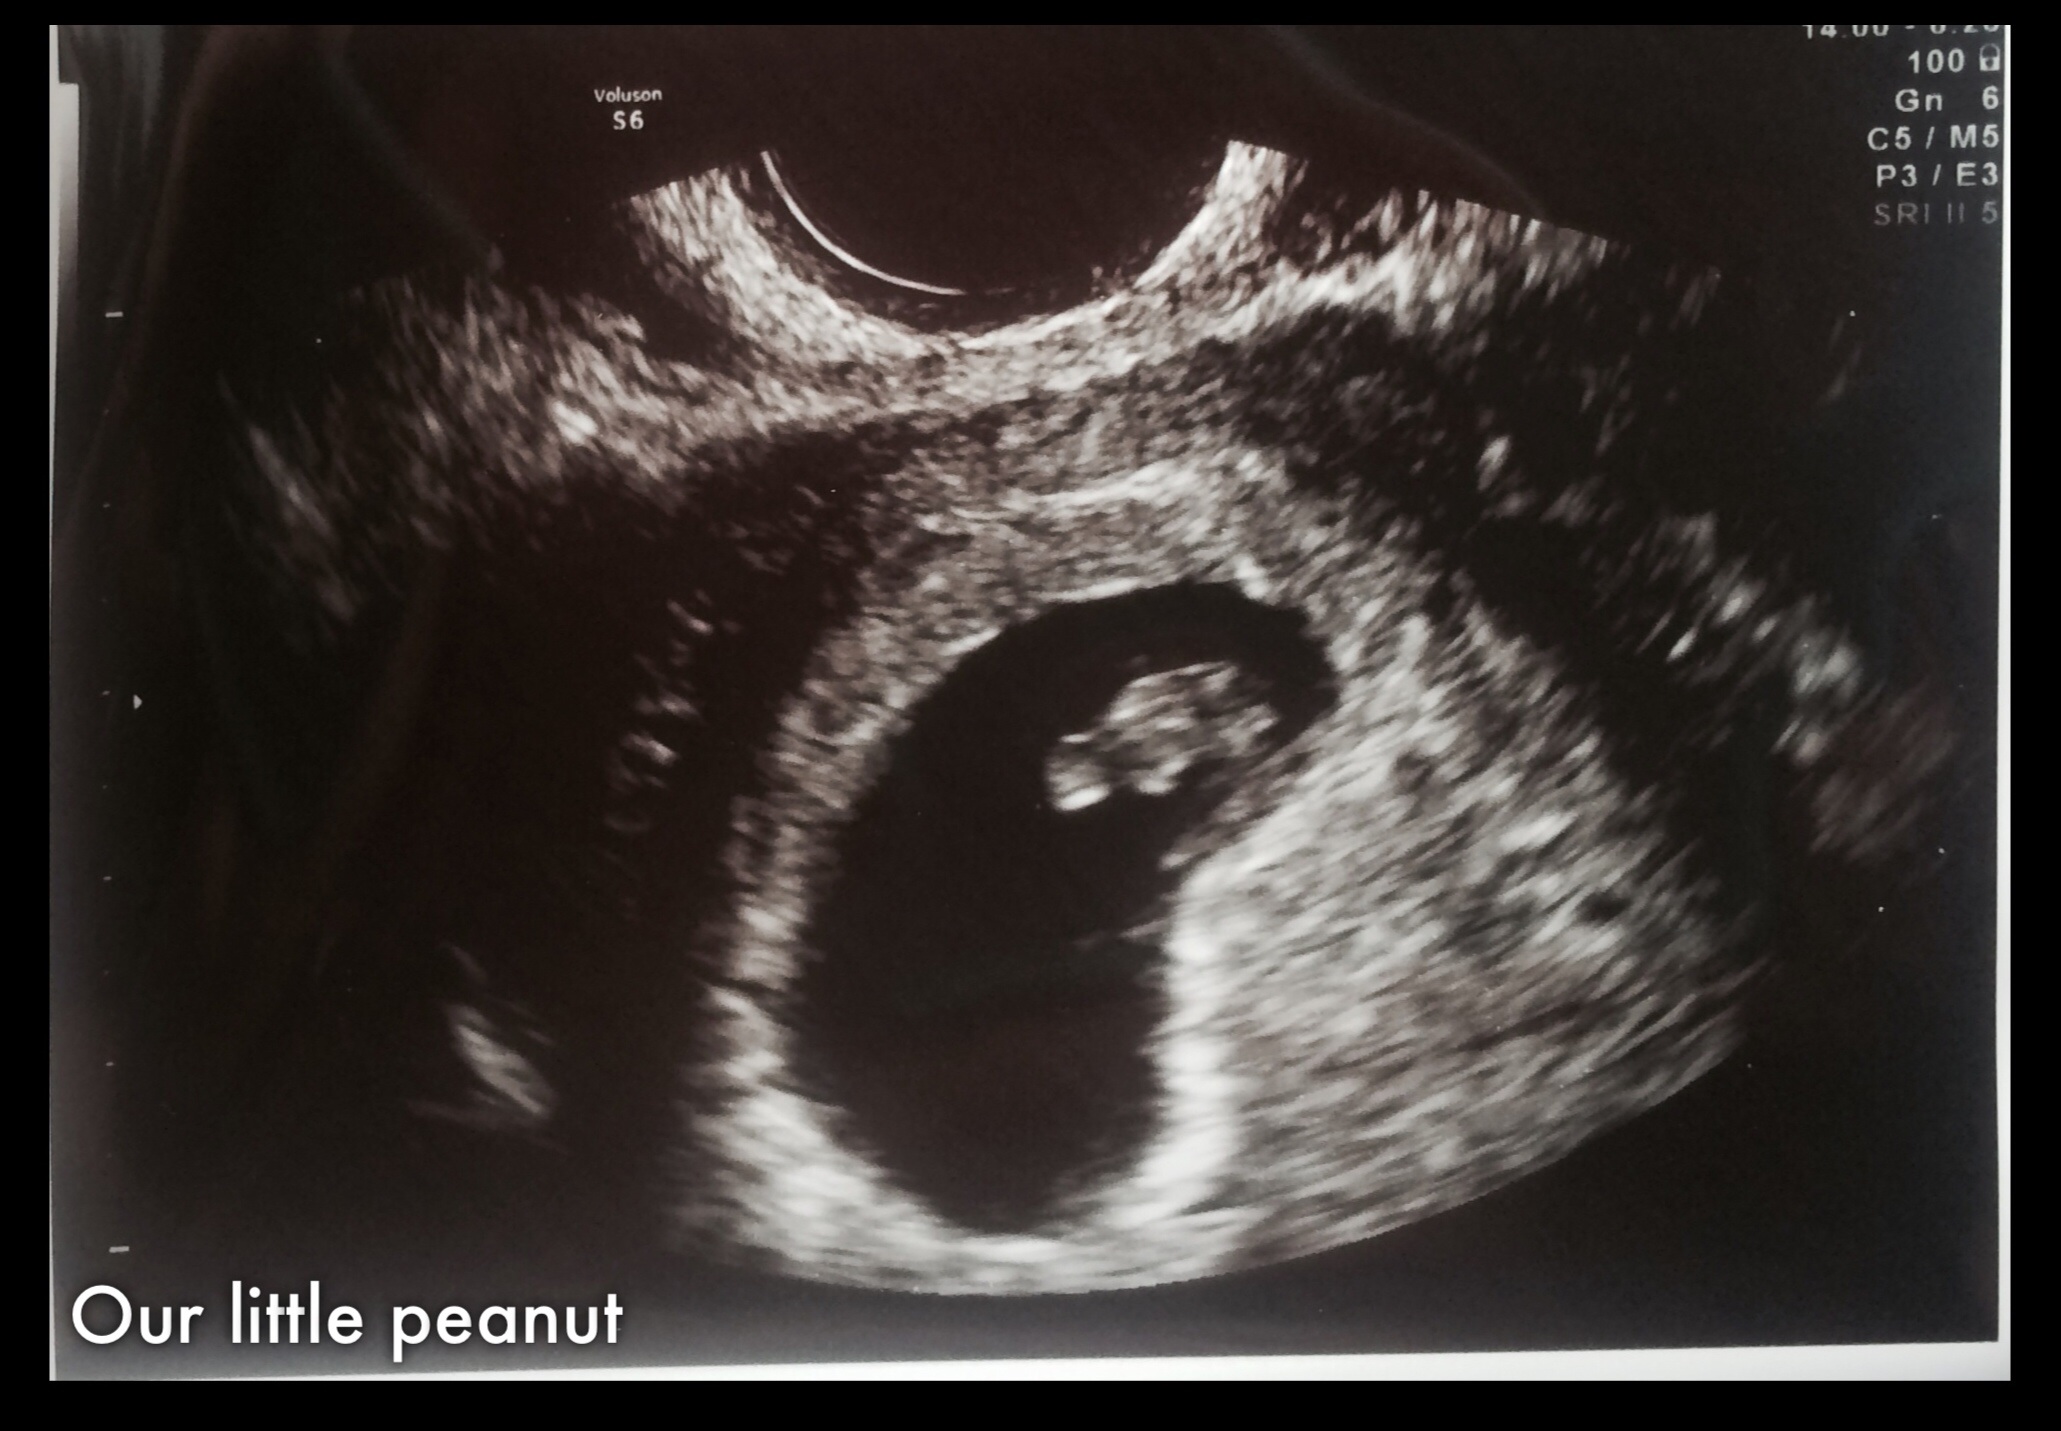

It breaks my heart that there have been so many losses today. Sending love to everyone. Here's our pic from last week at 6w3d. Can't wait to see the changes this week!

Here's our pic from last week at 6w3d. Can't wait to see the changes this week!